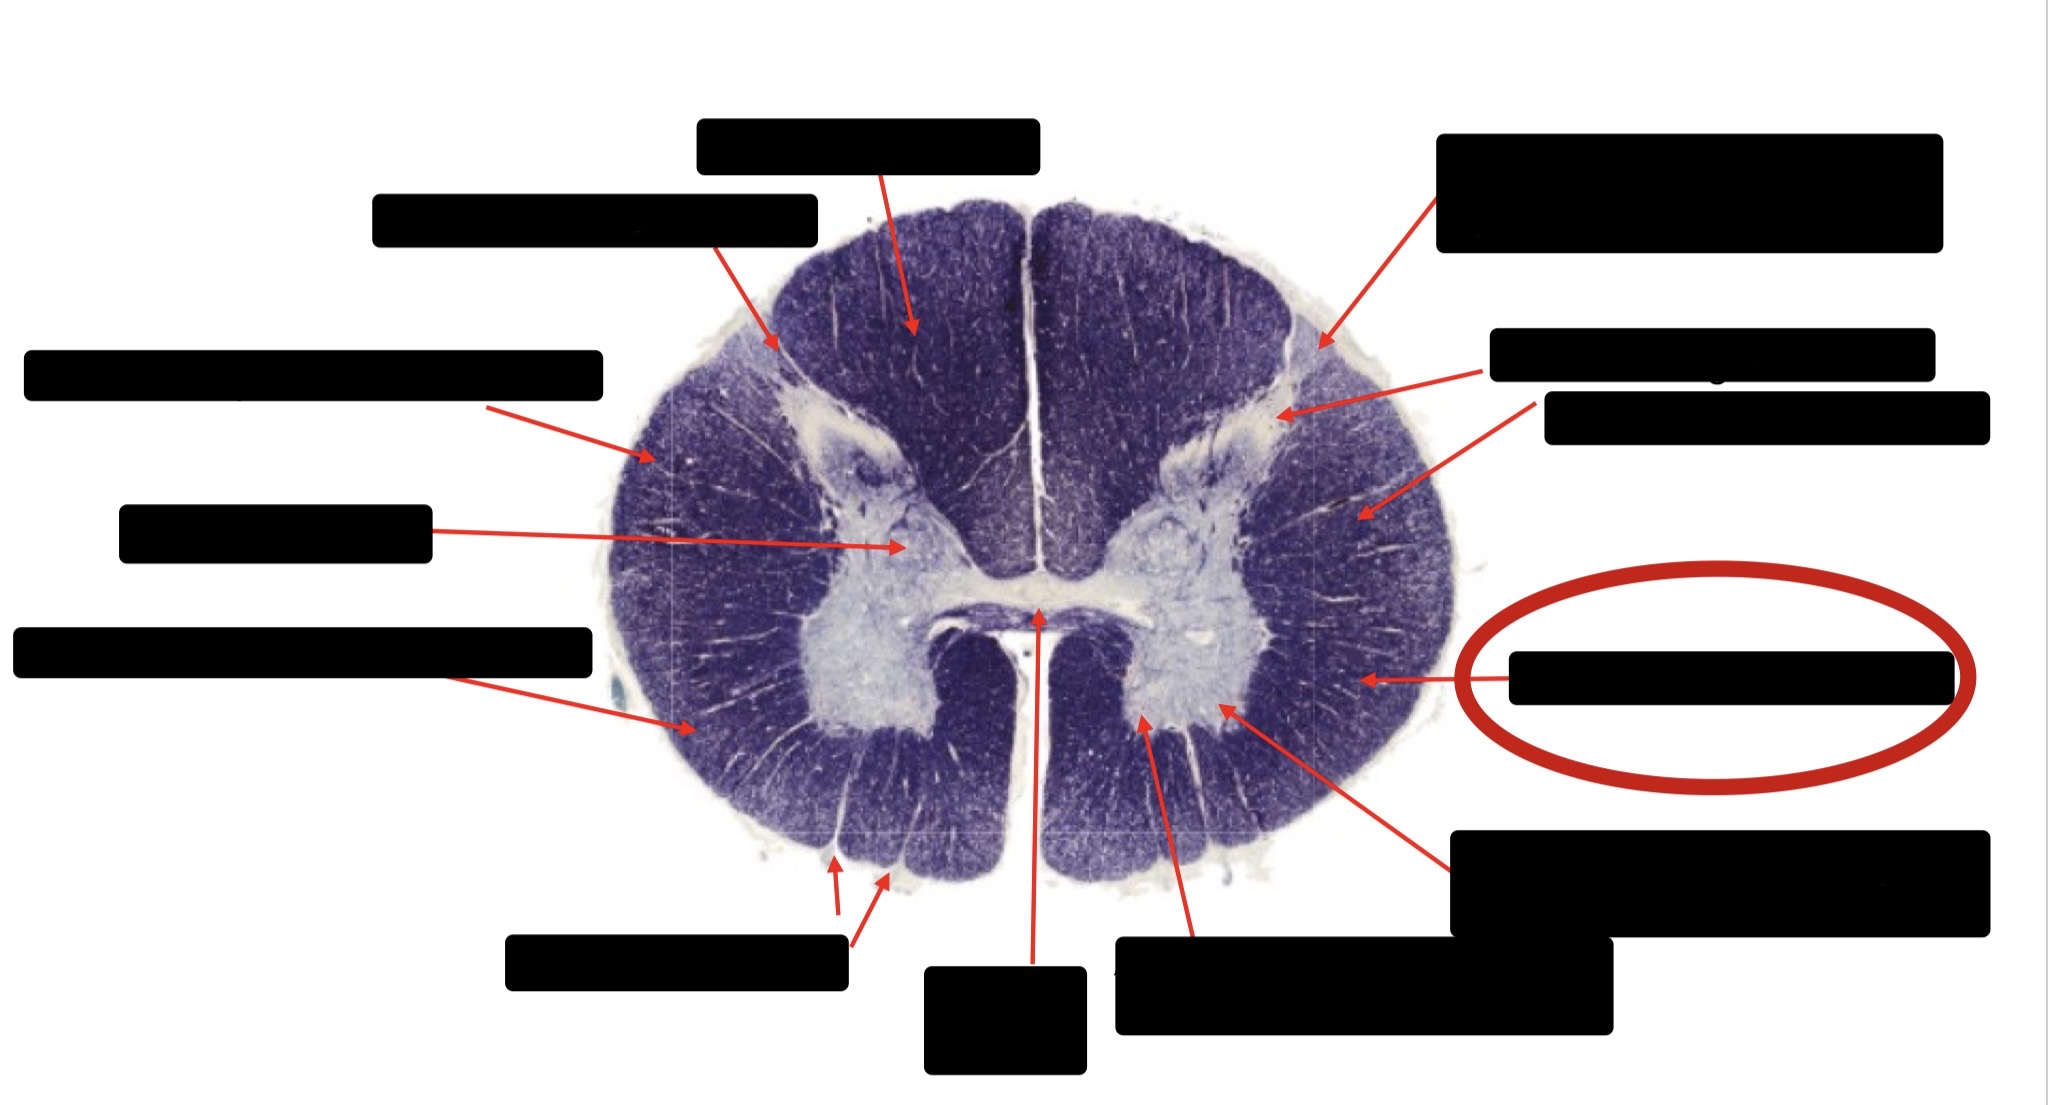

Posterior Column

Large Fiber Entry Zone

Posterior Spinocerebellar Tract

Clarke’s Nucleus

Anterior Spinocerebellar Tract

Ventral Root Fibers

Central Canal

Lissauer’s Tract & Small Fiber Entry Zone

Substantia Gelatinosa

Lateral Corticospinal Tract

Spinothalamic Tract

Anterior Horn Motor Neurons (Distal Muscles)

Anterior Horn Motor Neurons (Proximal Muscles)

Dorsal Rootlet

Lateral Horn

Spinothalmic Tract